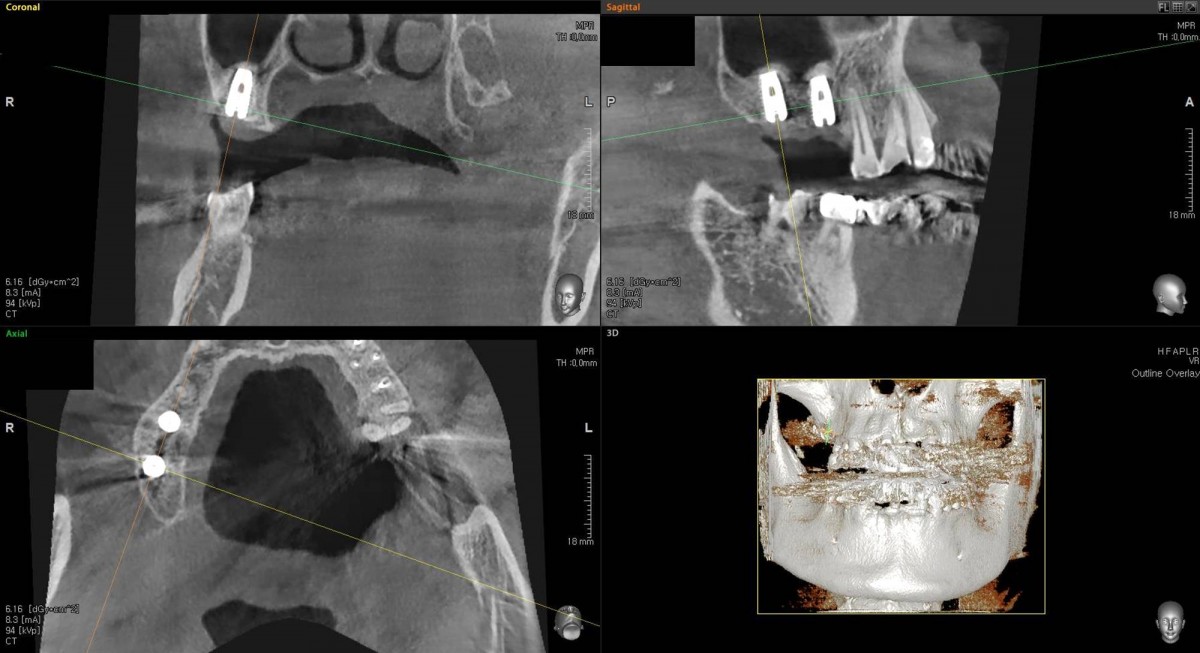

Socket Lift and Implant Placement in the right maxilla.

<GCacg> A 56-year-old male patient complained of pain in the right upper and lower jaws. And he wanted the upper first molar to be pulled out first.